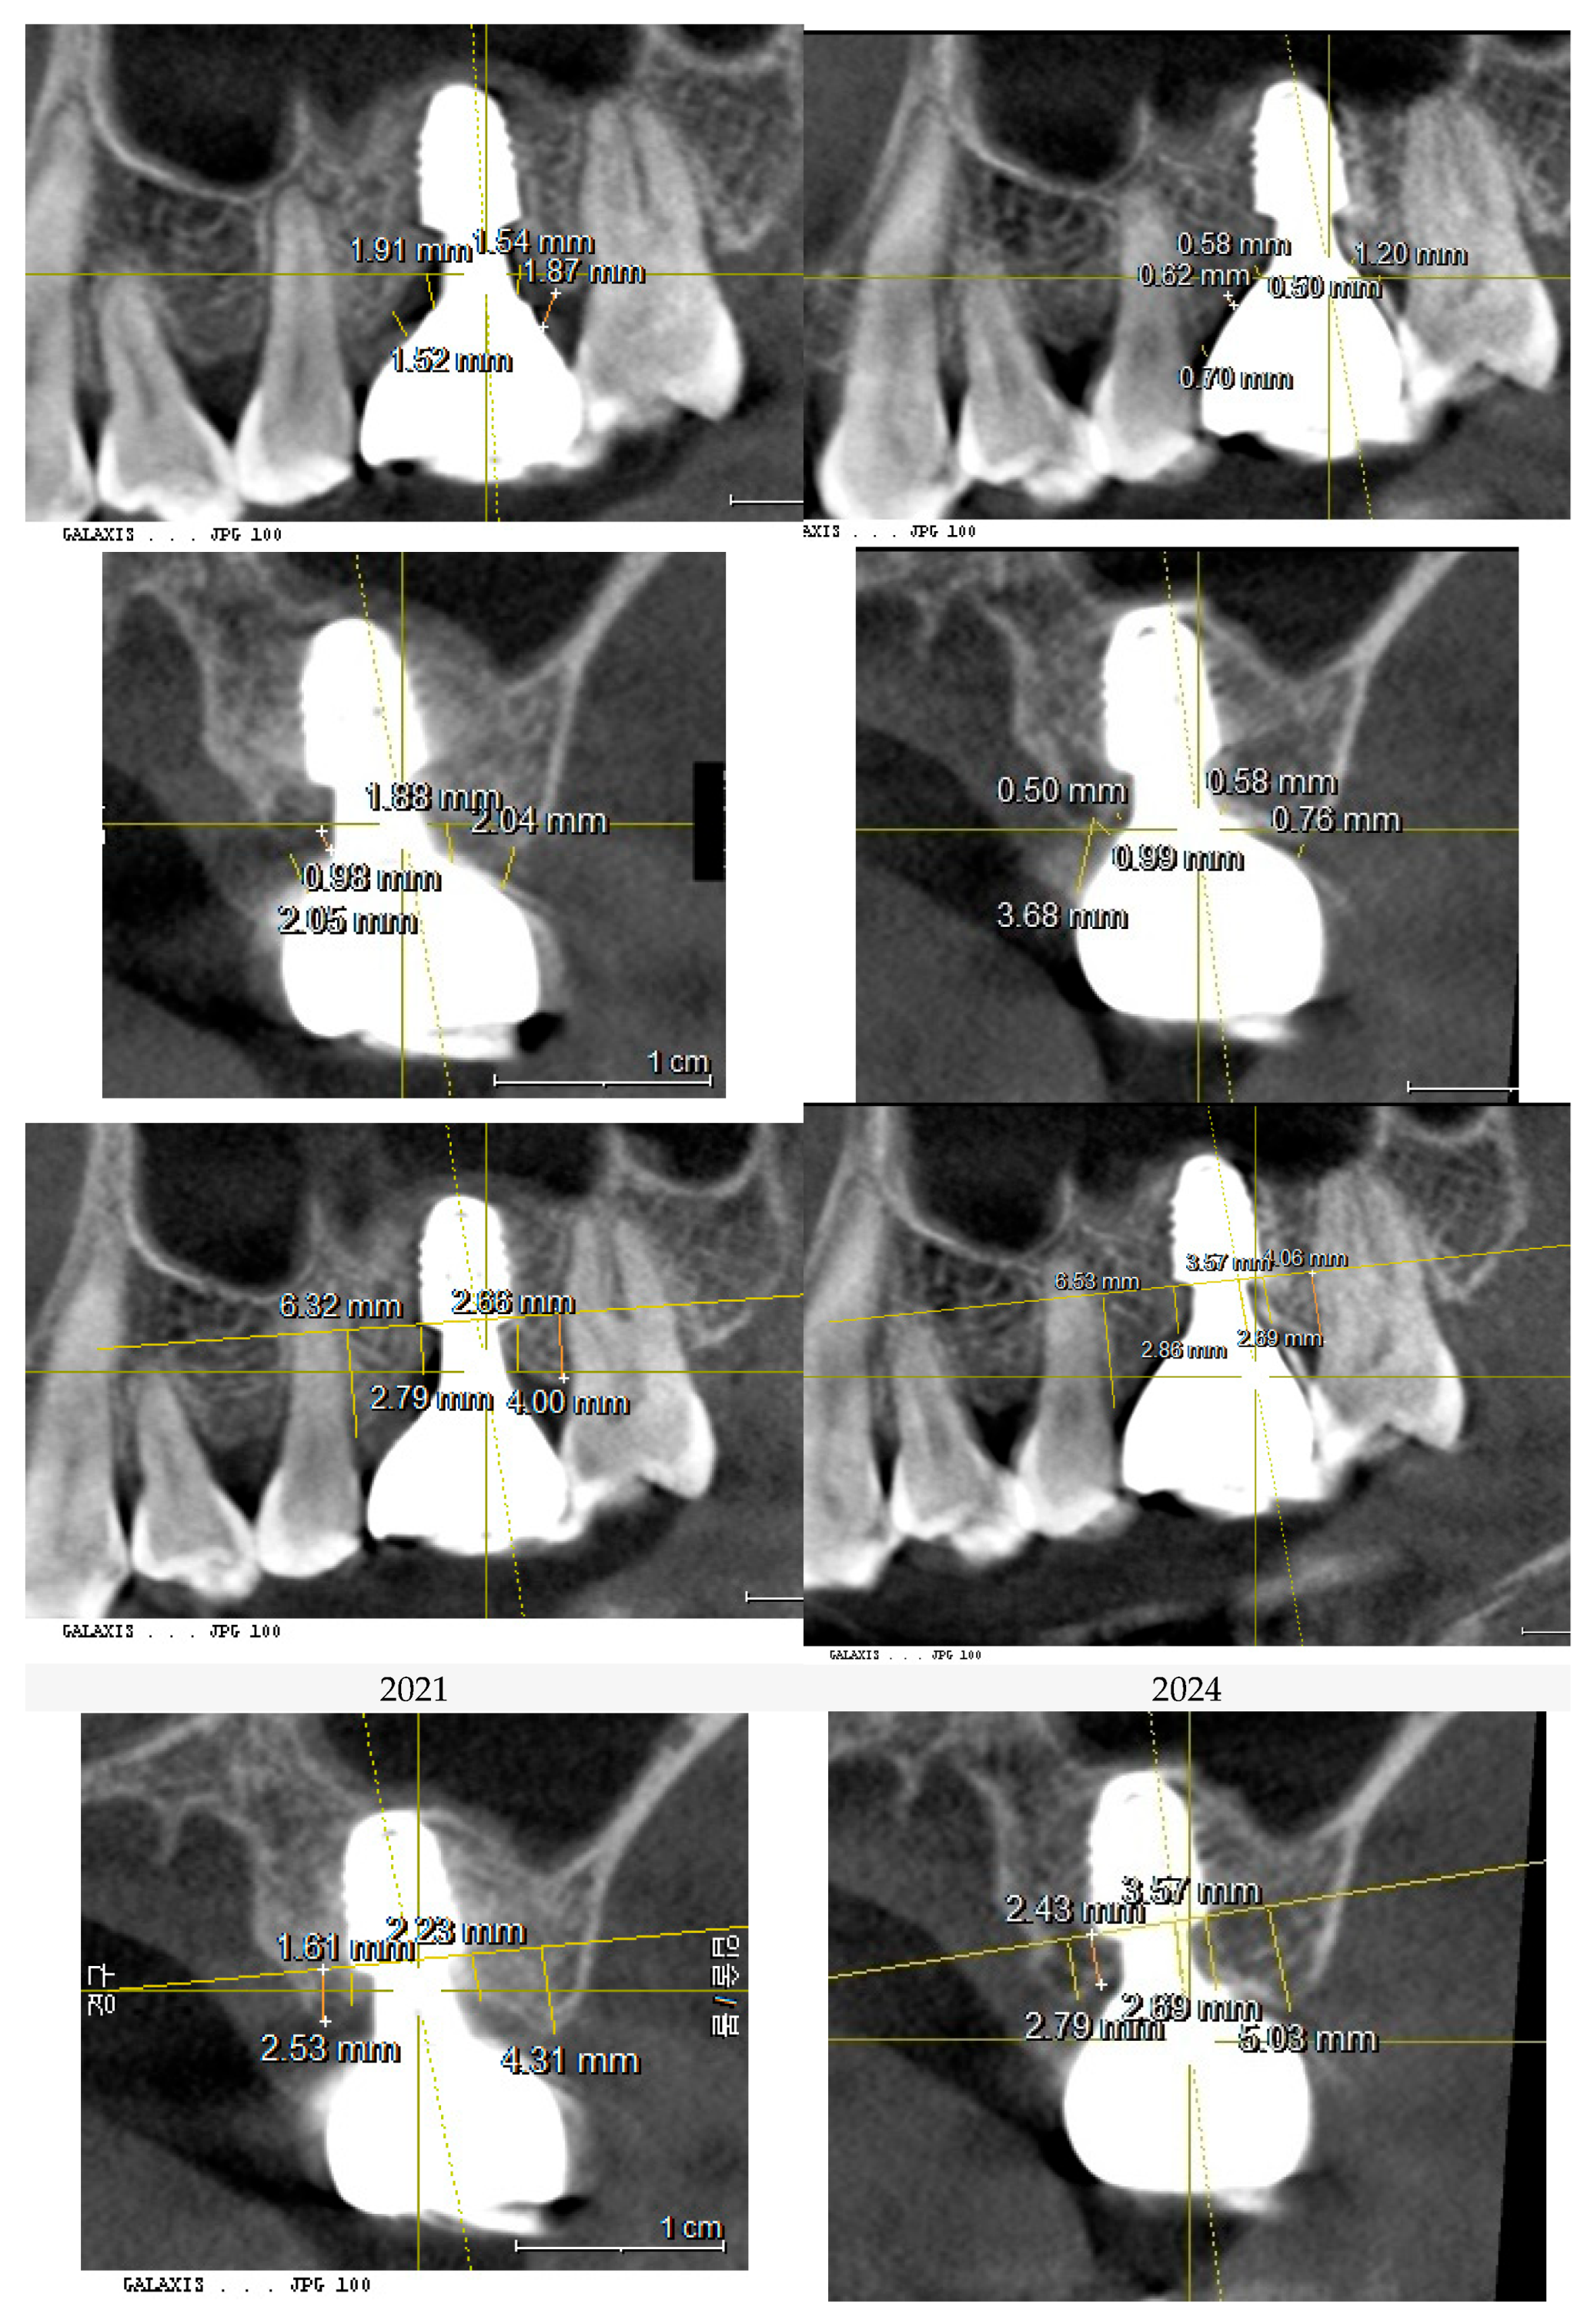

For the purpose of analyzing and comparing the peri-implant soft tissue structure and peri-implant bone topography, a CBCT (Cone-Beam Computed Tomography) scan was performed. The analysis specifically focused on the Crest to Restoration Distance (CRD), which represents the vertical distance between the implant restoration and the underlying crestal bone. The results of this analysis are summarized in Table 1. (Table 1)

The Crest to Restoration Distance (CRD) refers to the vertical space between the underlying crestal bone and the overlying implant restoration. To assess the dimensional variations along the implant interface, CRD is measured at two specific locations: centrally (cCRD) and peripherally (pCRD).

The results showed that the CRD for the upper left first molar implant was consistently larger than that for the lower right first molar implant. Specifically, the difference in central CRD (cCRD) measured 0.97 mm (1.48 mm – 0.51 mm), and the difference in peripheral CRD (pCRD) measured 0.90 mm (1.97 mm – 1.07 mm). Since comparable CBCT-based CRD measurements are not available in the existing literature, a clinical study by Won, which analyzed CRD (or Soft Tissue Thickness, STT) in 20 cases of subcrestally placed implants with stable outcomes over more than two years, was used as a reference. This analysis reported an average pCRD of 0.6 mm and an average cCRD of 0.3 mm (Table 2).

These two implant sites serve as a comparison for a split-mouth study. CBCT scans taken in 2021 and 2024 were utilized for a three-dimensional analysis of peri-implant soft tissue and bone structure.

Measurements of CRD changes for both implant sites (control and treatment) were conducted using Cone Beam Computed Tomography (CBCT). The analysis focused on parameters such as Crest to Restoration Distance (CRD), Depth of Placement (DP), and other structural features using CBCT imaging, complemented by clinical assessments. The primary objective was to evaluate how changes in CRD correlate with peri-implant health and disease, particularly in managing peri-implant mucositis.

The CRG and DP measurements for the upper left first molar implant and the lower right first molar implant were taken in 2021 and 2024. The averages for each measurement were calculated and compared over time. The results are summarized in Table 3, Table 4, Table 5, Table 6, Table 7 and Table 8. (Table 3, Table 4, Table 5, Table 6, Table 7, Table 8)

Figure 7 and Figure 8 illustrate the radiographic changes observed from 2021 to 2024 at the lower right first molar implant site (control site) and the upper left first molar implant site (experimental site), respectively. (Figure 7, Figure 8) The clinical photographs taken in 2024 (Figure 9) depict the final results, showcasing both a stable and natural appearance for both implant sites.

Figure 7. This image illustrates the X-ray measurements conducted on the lower right first molar implant, comparing data from 2021 and 2024.

Preprints 151394 g007

Figure 8. This image illustrates the X-ray measurements conducted on the upper left first molar implant, comparing data from 2021 and 2024..

Preprints 151394 g008